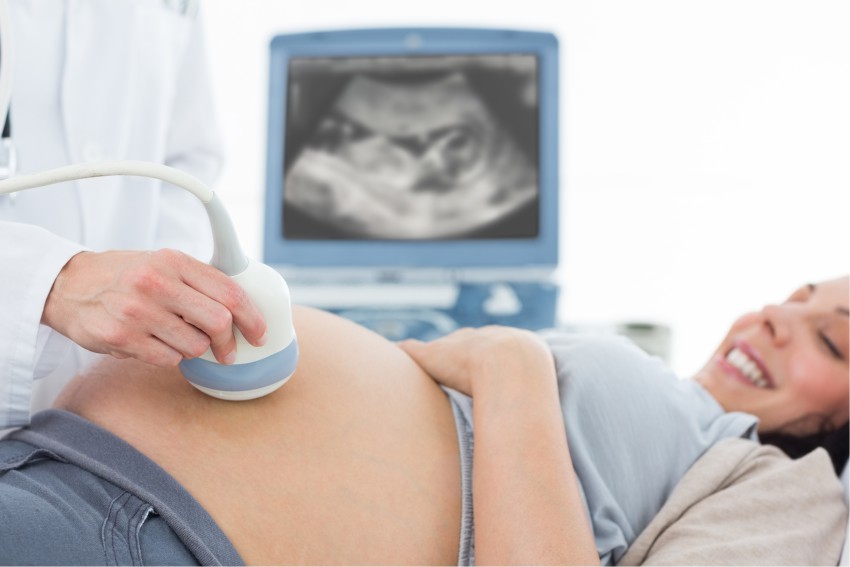

Doppler na Obstetrícia: Como Esse Exame Pode Prevenir Complicações na Gravidez?

O ultrassom Doppler é uma ferramenta essencial na obstetrícia moderna, permitindo avaliar o fluxo sanguíneo entre mãe e bebê. Esse exame contribui para a identificação precoce de complicações na gravidez, garantindo um acompanhamento mais seguro e um tratamento adequado quando necessário.